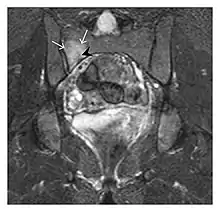

The greater tuberosity of the humerus is also an illustrative location of occult fractures. The osseous injury may follow seizures, glenohumeral dislocation, forced abduction, or direct impaction. They are commonly discovered on MRI in symptomatic patients with suspicion of rotator cuff tear. Coronal images are best suited for detection. They appear as crescentic oblique lines surrounded by a bone marrow edema pattern (Figure 5). The rotator cuff must be inspected since associated ligamentous lesions are common. In the ankle, malleoli and tarsal bones should be checked carefully for any cortical disruptions and radiolucent lines that may reveal a fracture. Awareness of the exact location of the pain will help direct the attention of the interpreter when searching for very subtle signs of fracture (Figure 6).[1]

Proximal femoral fractures usually occur in osteoporotic patients, and their signs include subtle neck angulation, trabecular angulation, and subcapital impaction line. A frog-leg lateral view may be helpful if the greater trochanter is short enough. However, positioning can be difficult because of hip pain. In patients with strong suspicion of proximal femoral fracture and negative radiographs, MRI limited to coronal T1 W images and scintigraphy can be highly valuable (Figures 13 and 14). Such an option, with limited examination time, is cost-effective and allows reliable exclusion or confirmation of the diagnosis, preventing an unnecessary stay at the hospital or delayed treatment. Moreover, MRI helps to detect soft tissue abnormalities which are more frequently seen in femoral, acetabular, and pubic injuries than sacral lesions. Concomitant fractures are also frequently seen in typical pelvic sites.[1]

a

b

Figure 13: Partial osseous avulsion of the gluteal muscles at the greater trochanter in a 59-year-old man who presented with the right hip pain without a history of trauma. Lauenstein view and anteroposterior and radiographs (not shown) did not show an obvious fracture line or disruption of bony contours in the acetabulum or the right femoral neck. (a) Coronal T1-weighted MRI displays an incomplete fracture line extending partially from the greater trochanter (arrow). (b) Coronal short tau inversion recovery MRI shows heterogeneous hyperintensity in the same region (arrow) as well as hyperintensity within the gluteus medius and minimus muscles (arrowheads) consistent with tissue edema and hematoma.[1]